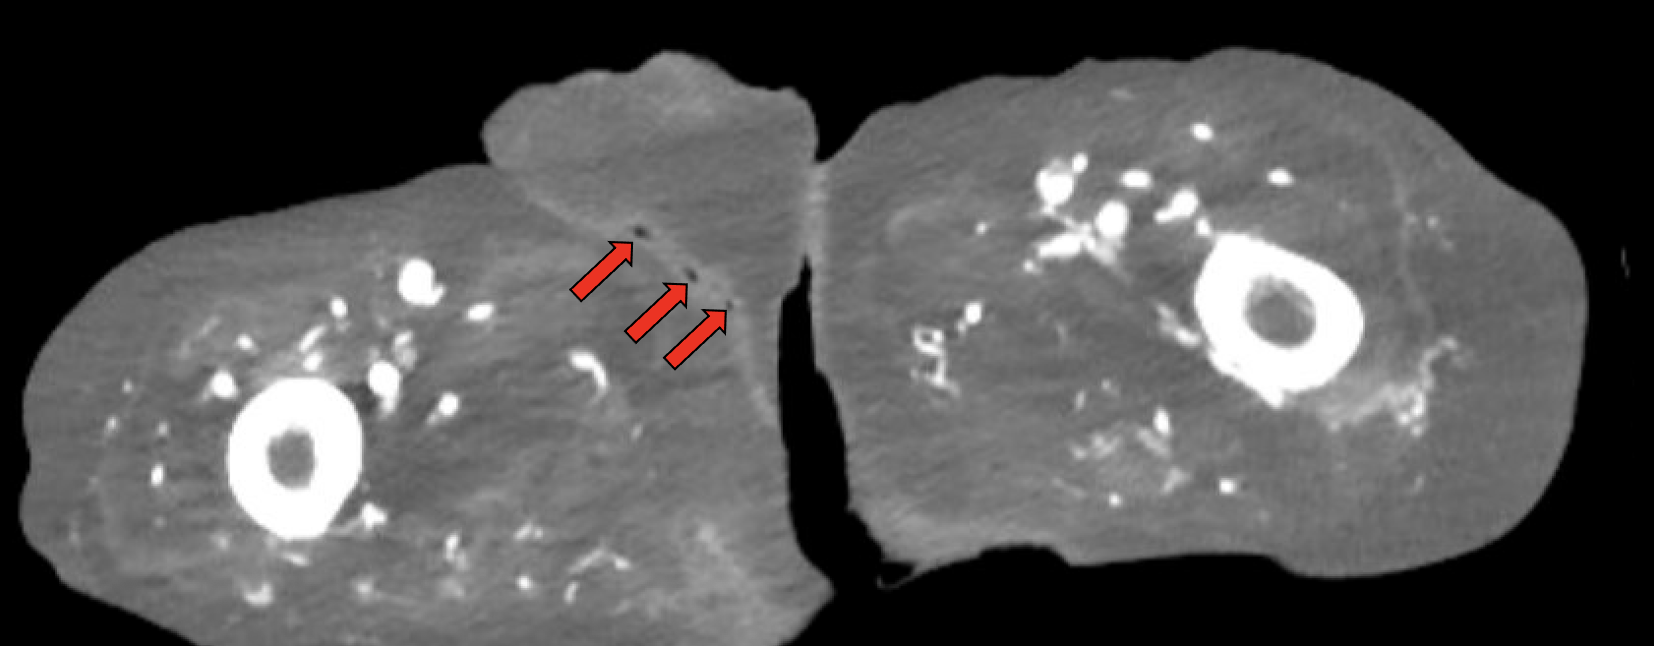

Fournier’s gangrene is a well-established surgical emergency as patients can decompensate rapidly, resulting in significant morbidity and mortality. We describe a case in which a 54-year-old medically complex male presented to the emergency department (ED) with a primary complaint of abdominal pain after a therapeutic paracentesis was performed by interventional radiology just prior to arrival. Upon further questioning, the patient reported scrotal pain that had developed over three to four days. On exam, the patient was well-appearing although he did have scattered scrotal masses with chalky white purulence. Given the relatively quick development, an atypical presentation of Fournier’s gangrene was suspected, and the patient was started on antibiotics with urology immediately consulted. Imaging was concerning for subcutaneous gas. The patient was subsequently taken to the operating room (OR) for debridement, where Fournier’s gangrene was confirmed by surgical investigation and culture. Significant lessons from the case include the importance of early identification of Fournier’s gangrene and having a low threshold to start treatment in coordination with a surgical service for atypical presentations.